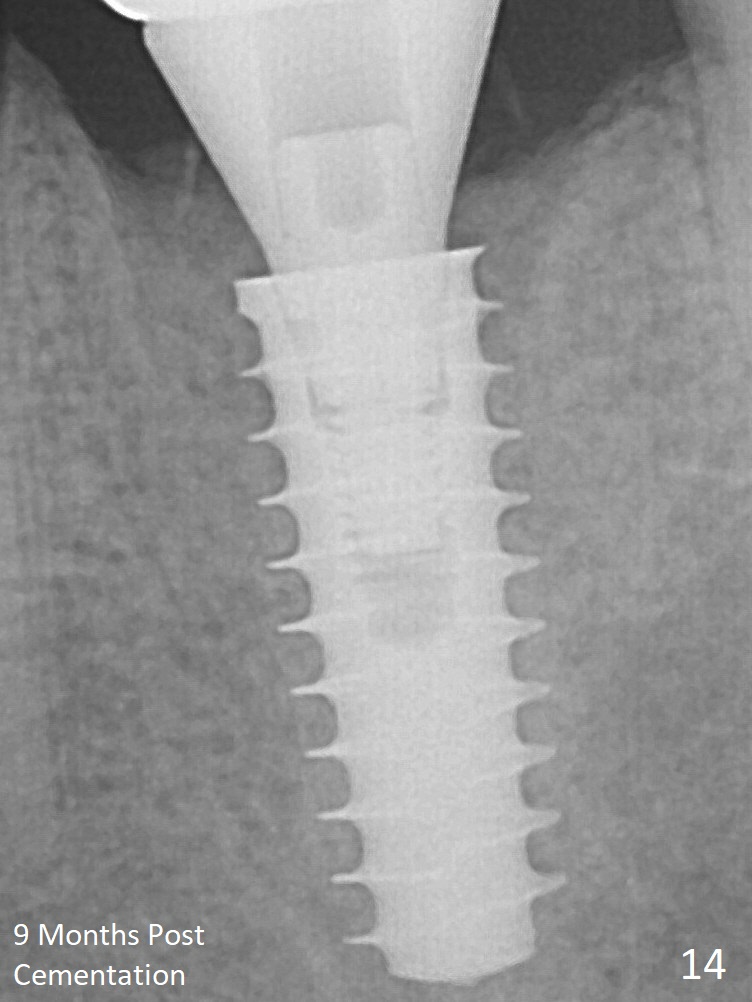

New bone has apparently covered the implant plateau 8 months postop (3 months post cementation (Fig.13 arrows)). The lower two-thirds of socket have disappeared. Bone density between threads increases 9 months post cementation (Fig.14).